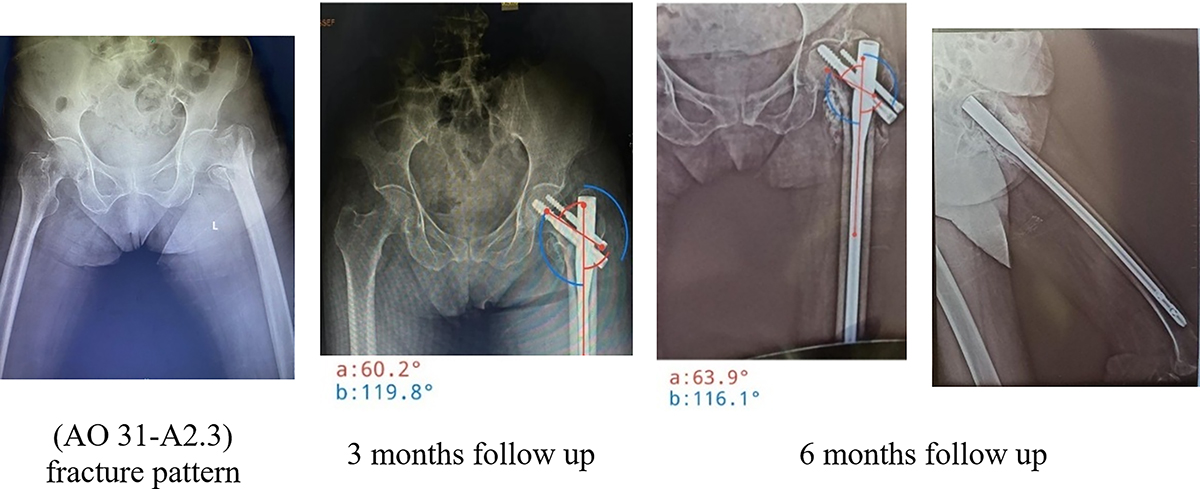

Figure 5

Long CMN varus collapse and screw back out.